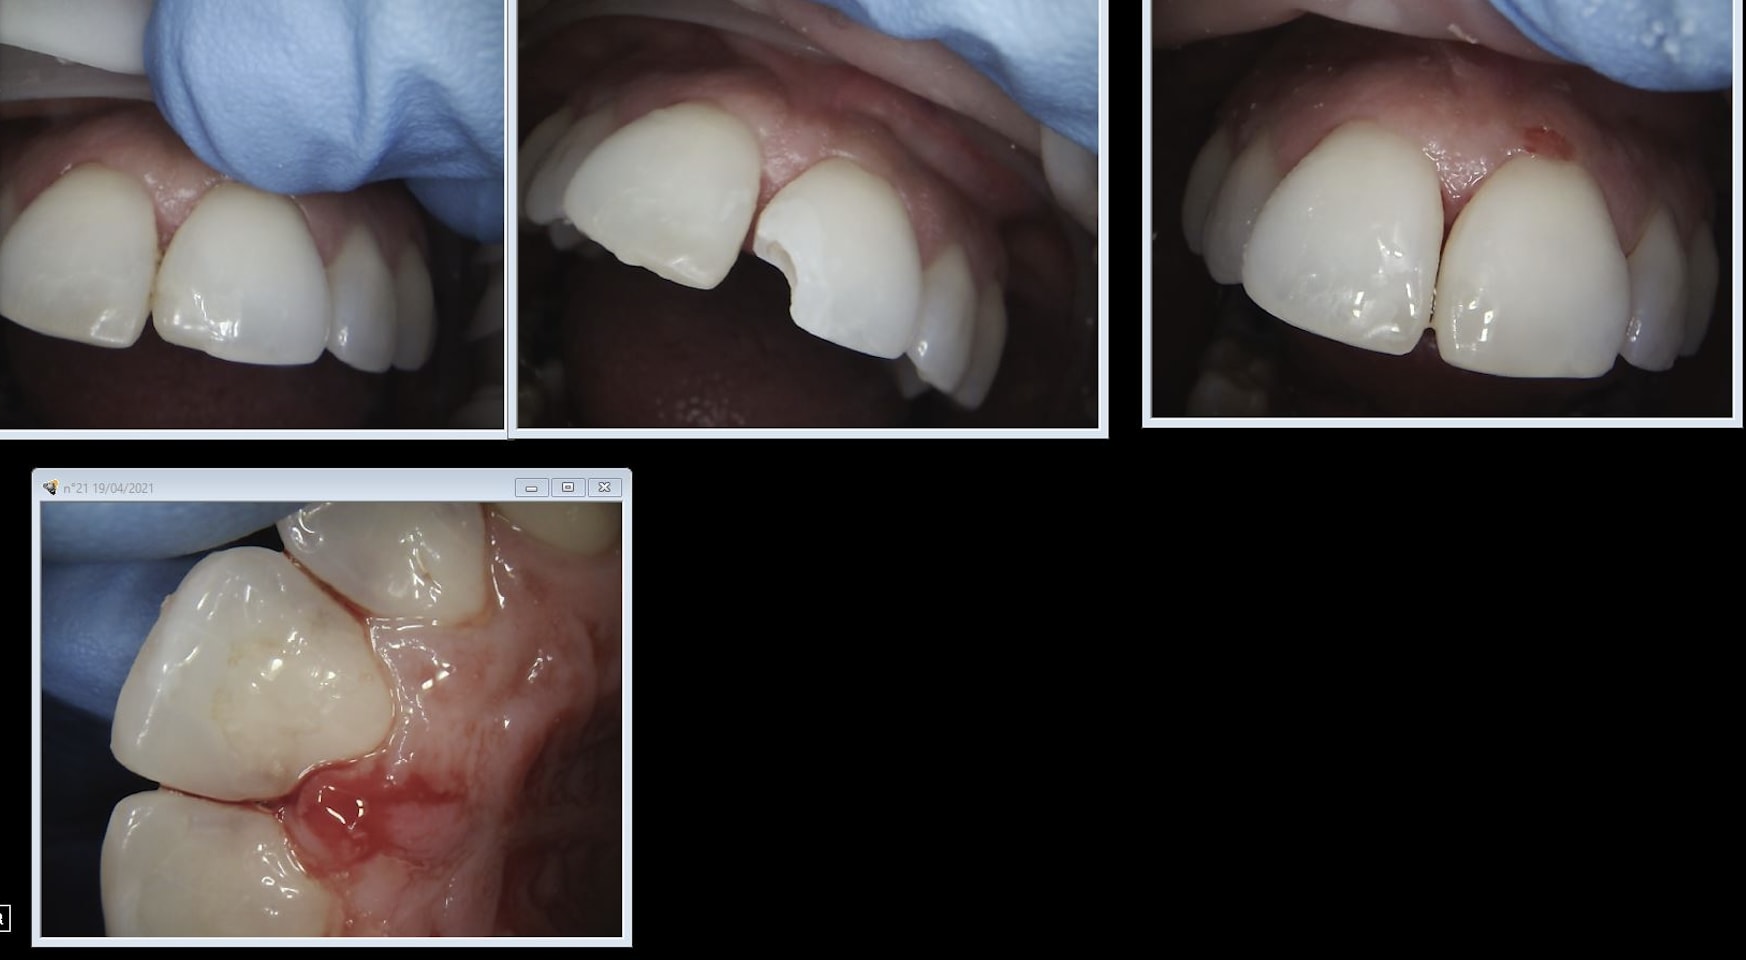

L'endo de 21 très couleur collectiviste locale. Encore un canal calcifié. Il y a casa qui va te dire que c'est top pas de 4ième aux innocents les mains pleines. -)

Zw0qu7pobx1l4cqa9cr7ycob8f93 - Eugenol